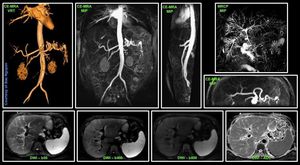

Liver specific contrast agent Primovist/Eovist @ Siemens 3T Skyra#Siemens_MRI #siemens #mri #primovist #skyra #3t #gadolinium #liver_imaging